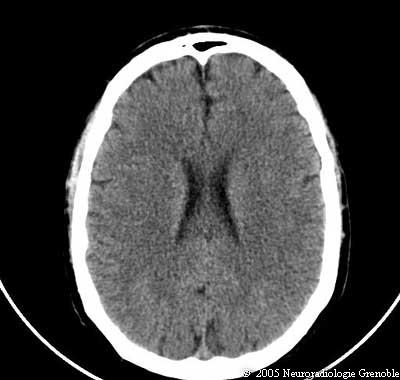

Radioanatomie TDM de l'encéphale

TDM cérébrale sans injection